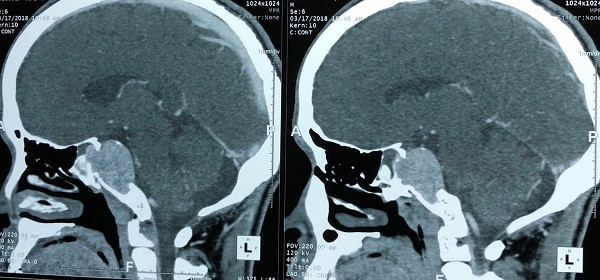

Tại Bệnh viện K, kết quả chụp chiếu cho thấy bệnh nhân B. có khối u não nền sọ vùng dốc nền, kích thước lớn 3x4cm. Sau khi hội chẩn, các bác sĩ nhận định đây là ca mổ phức tạp vì khối u lớn liên quan đến nhiều chức năng quan trọng như: thân não, mạch máu não, tuyến yên, và ở đáy sọ. Đặc biệt, việc lựa chọn đường mổ phải được tính toán kỹ lưỡng nhằm đảm bảo lấy tối đa khối u và an toàn cho người bệnh.